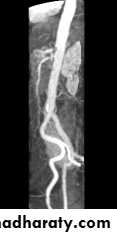

Special MRI studies

MR angiography :non-invasive imaging of the vascular tree , In normal circumstances flow effects cause unwanted artefacts, but in MRA these phenomemna are used advantageously ,

2D ToF

By acquiring manyindividual slices long

vessels may be covered

easily. The resulting slices

are then combined and

viewed as a maximum

intensity projection (MIP)

in any orientation.

Vascular Techniques

2D ToFThe resultant image

may be rotated, paged

and manipulated to

demonstrate the

optimum viewing

plane.

(With IVI or AW

software packages)